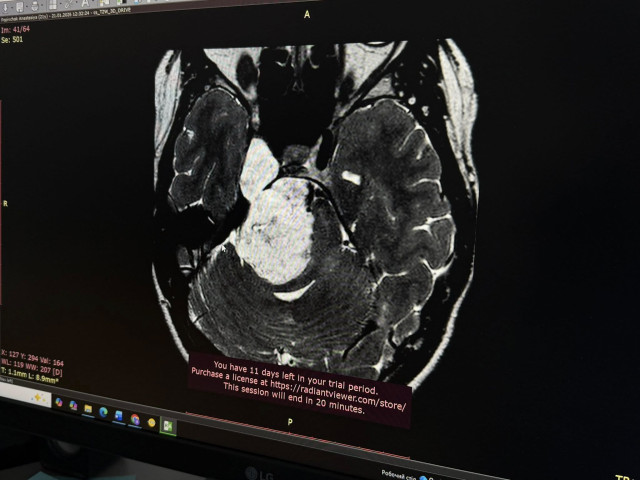

За кілька місяців стан Анастасії різко погіршився: з’явилися постійні нудота та втома, а до зниження гостроти зору додалась ще й косоокість. Крім цього, кілька разів в неї повністю зникав слух на праве вухо – і це лякало дівчину найбільше. Почались порушення координації. Тож Анастасія нарешті звернулася за допомогою. Польські спеціалісти провели МРТ і виявили у молодої українки велику пухлину головного мозку.

«Я була в шоці. Це було дуже неочікувано. Я розглядала різні варіанти, але не такий. Проте рук не опустила, зрозуміла, що потрібно шукати вихід і лікарів, яким можна довіритися», — згадує Анастасія.Довірилася своїм – львівським нейрохірургам Лікарні Святого Пантелеймона, а ті своєю чергою зіткнулися з доволі рідкісним випадком розташування пухлини. Виявилося, що у мозку Анастасії розросталася холестеатома – доброякісне новоутворення, яке зазвичай виникає у середньому вусі. Натомість у цієї пацієнтки пухлина поширилася на дві з трьох черепних ямок: на задню та середню, що є вкрай нетиповим та небезпечним.

Холестеатома виросла до загрозливих розмірів – 6 на 3 сантиметри – та вже стискала стовбур мозку, що й пояснювало проблеми зі слухом, зором та координацією. Ба більше – в задній черепній ямці також розташовані і центри дихання та серцевої діяльності, а це вже становило пряму небезпеку для життя Анастасії. Вона просто могла перестати дихати. Треба було якомога скоріше видалити пухлину, однак її локалізація значно ускладнювала цю задачу, зазначають медики.